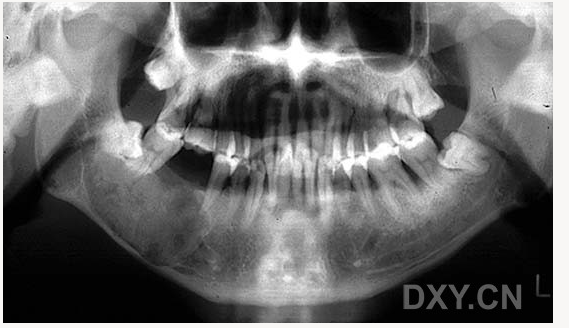

大理石骨?。ㄏ骂M骨有明顯的骨化影像,恒牙埋伏)

鼻竇炎(注意不要誤診呀)

良性成牙骨質(zhì)細胞瘤